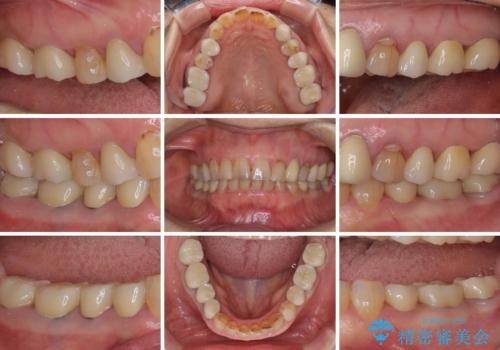

全ての奥歯の銀歯をセラミックに メタルフリー治療

途中体調を崩されてしまい、その間に仮歯が外れてしまうなど、治療期間が長引いてしまいました。

治療期間はかかってしまいましたが、念願のメタルフリーとなり、患者様には大変満足していただきました。

セラミック治療の注意事項(リスク・副作用など)

- 天然歯を削ります

- 硬い素材は天然歯を傷つけてしまう場合があります

- かみ合わせや歯ぎしりが強すぎる方はセラミックが割れてしまう可能性があります

- 自費診療(保険適用外治療)となります